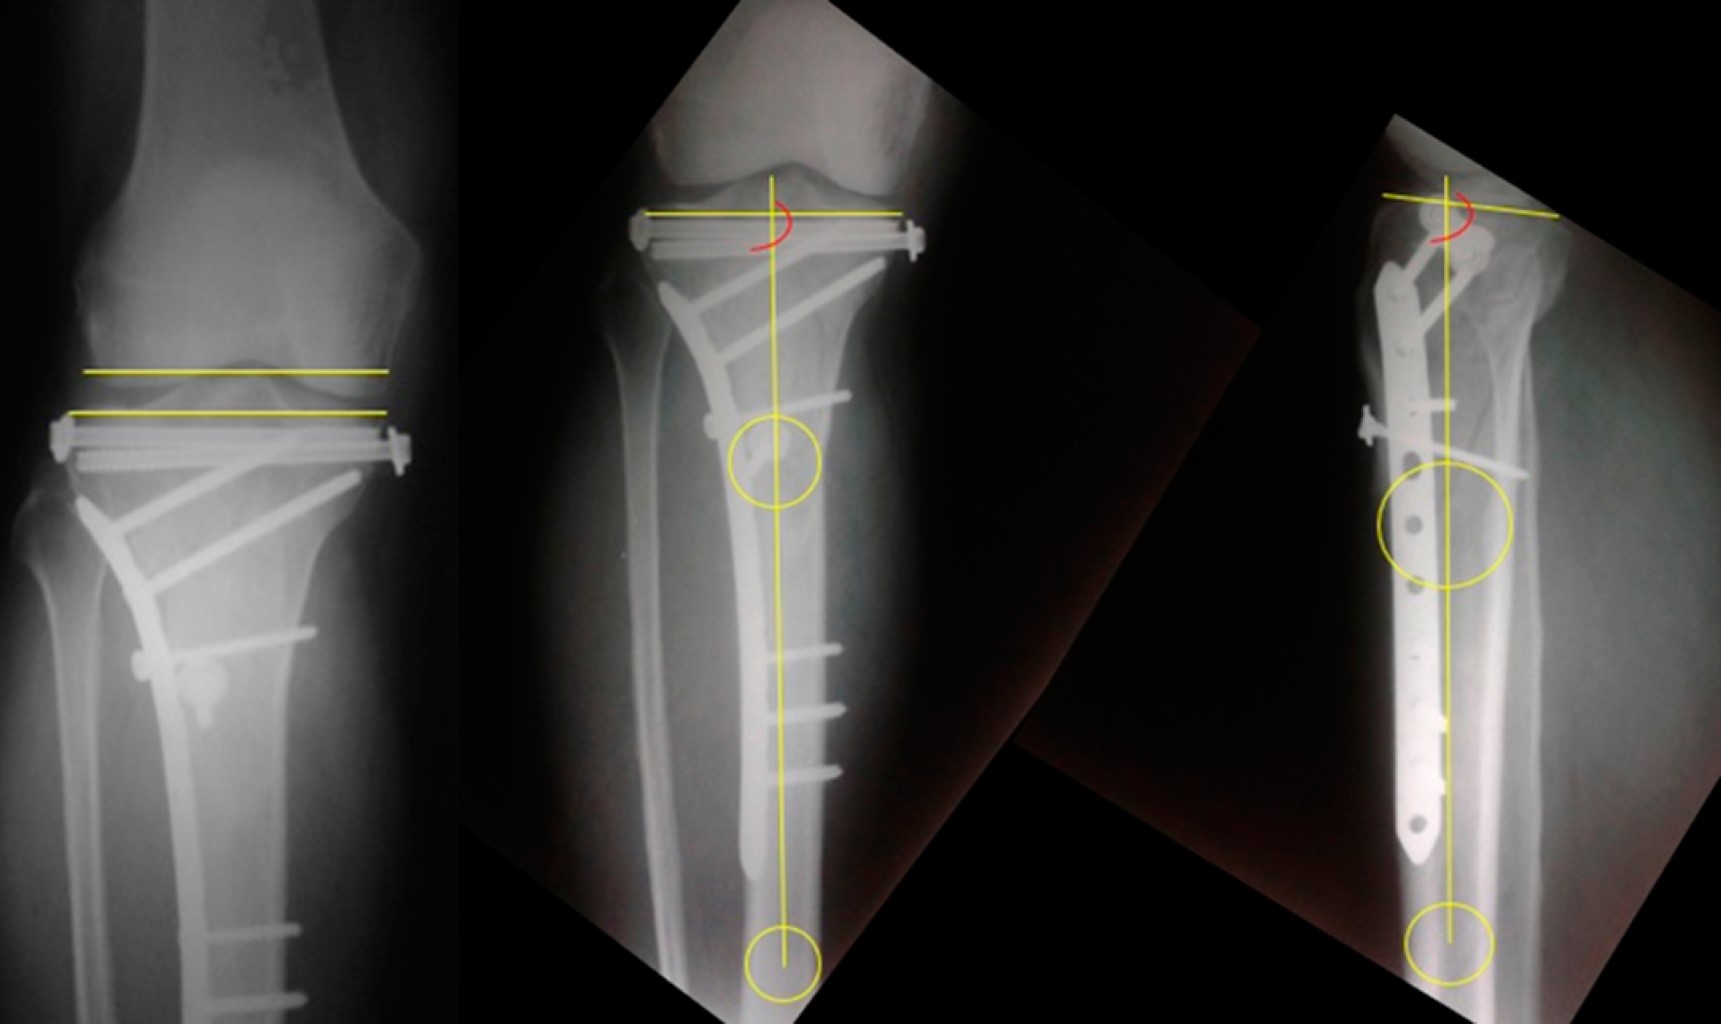

• 1. Medición del ensanchamiento postoperatorio del platillo tibial. Se determinó el desajuste condilar femoral/tibial lateral. Si el ensanchamiento de la tibia, medido en radiografías anteroposteriores (AP), correspondía a menos de 4% del ancho de la superficie articular femoral distal se consideró normal, siguiendo el criterio de Kumar (Figura 1).5

• 2. La medición de los ejes en el plano coronal que observa las desviaciones en varo/valgo y la inclinación posterior de la rodilla. Aquí utilizamos los criterios de Paley:12 el ángulo medial proximal de la tibia (AMPT) con valores normales comprendidos entre 85-90o y el ángulo proximal posterior de la tibia (APPT) entre 77-84o (Figura 1).

Análisis radiológico. De los casos, 45 (83.4%) no tuvieron alteraciones del eje en plano coronal, seis pacientes con excesivo varo (menos de 85o AMPT) y tres con excesivo valgo (más de 90o AMPT). La inclinación posterior de la rodilla, que manifiesta los desejes en plano sagital, fue aceptable en 41 (75.9%) pacientes (tres casos de APPT menor de 77o y 10 casos de APPT mayor de 84o). Además, 40 pacientes (74%) no tuvieron ensanchamiento articular postoperatorio excesivo.